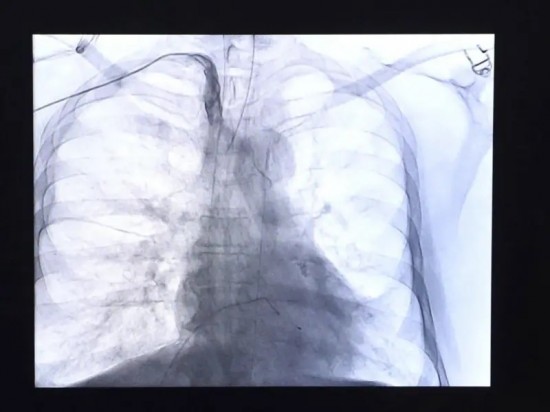

Enfermedades del corazón se mantienen como la primera causa de muerte en los mexicanos.

Con 100 mil 710 decesos durante el primer semestre del 2024, las enfermedades del corazón se mantuvieron como la principal causa de muerte de los mexicanos.

Ciudad de México.- Con 100 mil 710 decesos durante el primer semestre del 2024, las enfermedades del corazón se mantuvieron como la principal causa de muerte de los mexicanos.

Los hombres presentaron la mayor mortalidad con 53 mil 515 fallecimientos, frente a los 47 mil 187 que se registraron entre las mujeres.

De acuerdo al último reporte del Inegi publicado este 22 de enero para dar a conocer las cifras preliminares de las Estadísticas de Defunciones Registradas (EDR), la segunda causa de muerte fue la diabetes mellitus con 57 mil 986 casos y en tercer sitio se ubicaron los tumores malignos con 47 mil 439.